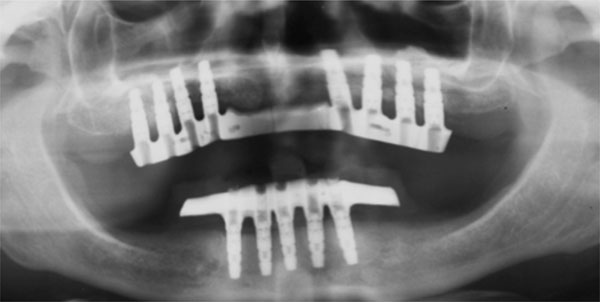

Fig. (12).

Follow-up orthopantomograph.

Follow-up

Clinical examination evaluated signs or symptoms of infection, loss of the grafted bone, dehiscence, and loss of dental implants. Radiological follow- up was performed by means of panoramic radiographs (Fig. 12). The patients had pre-operative panoramic radiographs, and post-operative radiographs at immediate post-operative follow-up, and at 3-month, 5-month, 12-month and yearly follow-ups thereafter. All radiographs were taken on the same machine and the radiographic exposure parameters remained unchanged for all the patients. The radiographic magnification factor was calculated based on the known length of the implant and the measurements obtained with the magnification scale were extrapolated to normal scale.

During the retrospective evaluation, a program (Image J, National Institute of Health, U.S.A.) was used to measure the mesial and the distal peri-implant bone loss around each implant. The values were obtained measuring the distance from the top of the implant head to the first visible bone- implant contact.